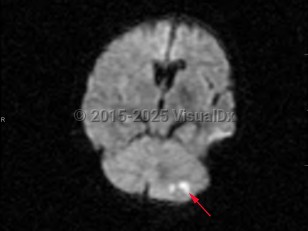

- Ischemic cerebellar strokes are predominantly either thrombotic or embolic. Thrombotic strokes are often caused by atherosclerosis, while embolic strokes are commonly cardiogenic (atrial fibrillation), septic, or due to coagulopathy.

- Hemorrhagic strokes can be intraparenchymal, due to hypertension, or secondary to subdural or subarachnoid hemorrhage.